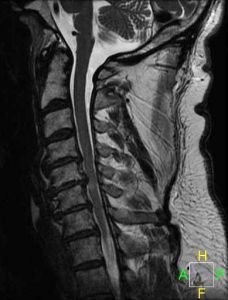

CERVICAL SPINAL STENOSIS